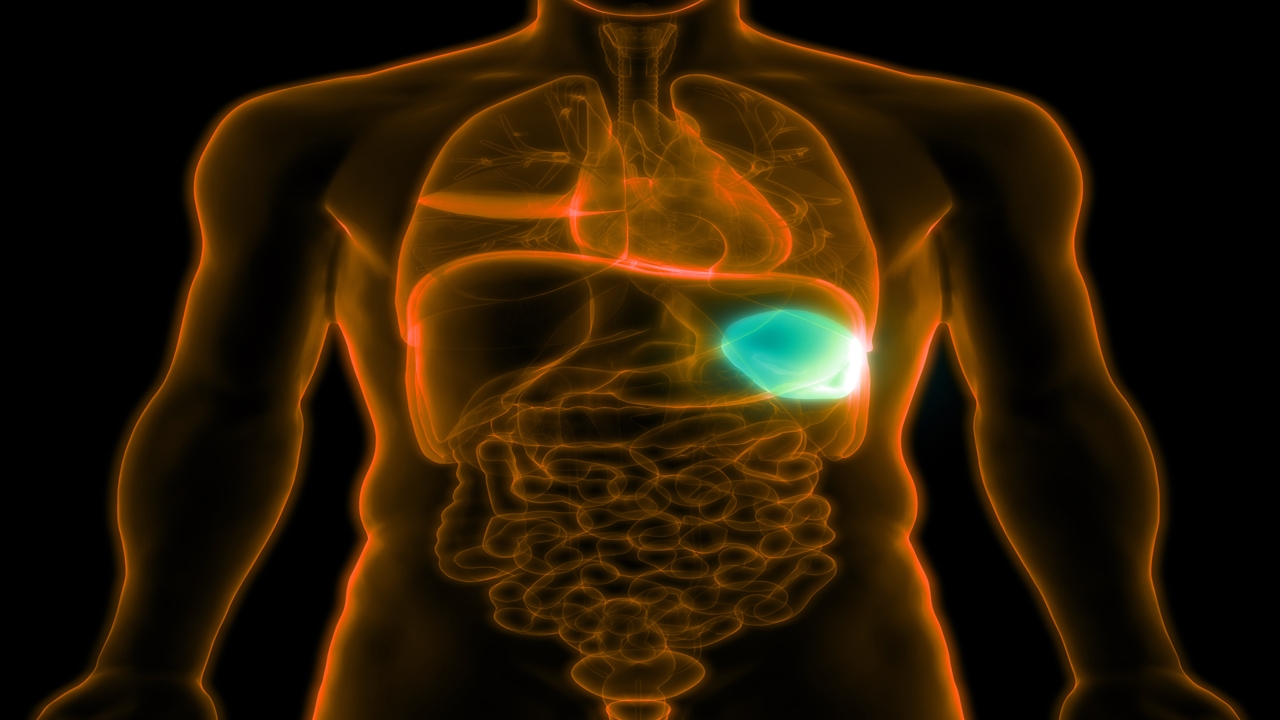

Upper Left Quadrant Pain